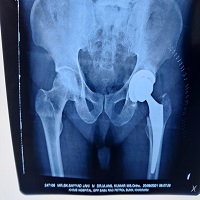

View TimetableHe has worked Contiental Hospital in Hyd, He has vast experience in Knee Hip Replacments.Successfully performed advanced surgeries like Knee,shoulder, Hip Replacemets,Trauma procedure Surgeries.